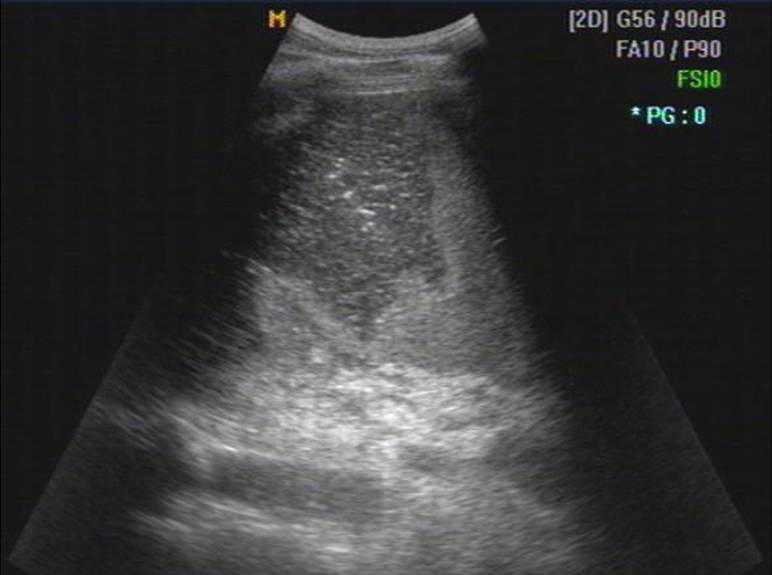

声像表现

1、脾大

2、急性期脾梗死

单发或多发,大小不一

单发者楔形,基底宽,凸面向包膜,尖端指向脾门

内部回声呈大片回声减低区

中央发生坏死液化出现无回声区